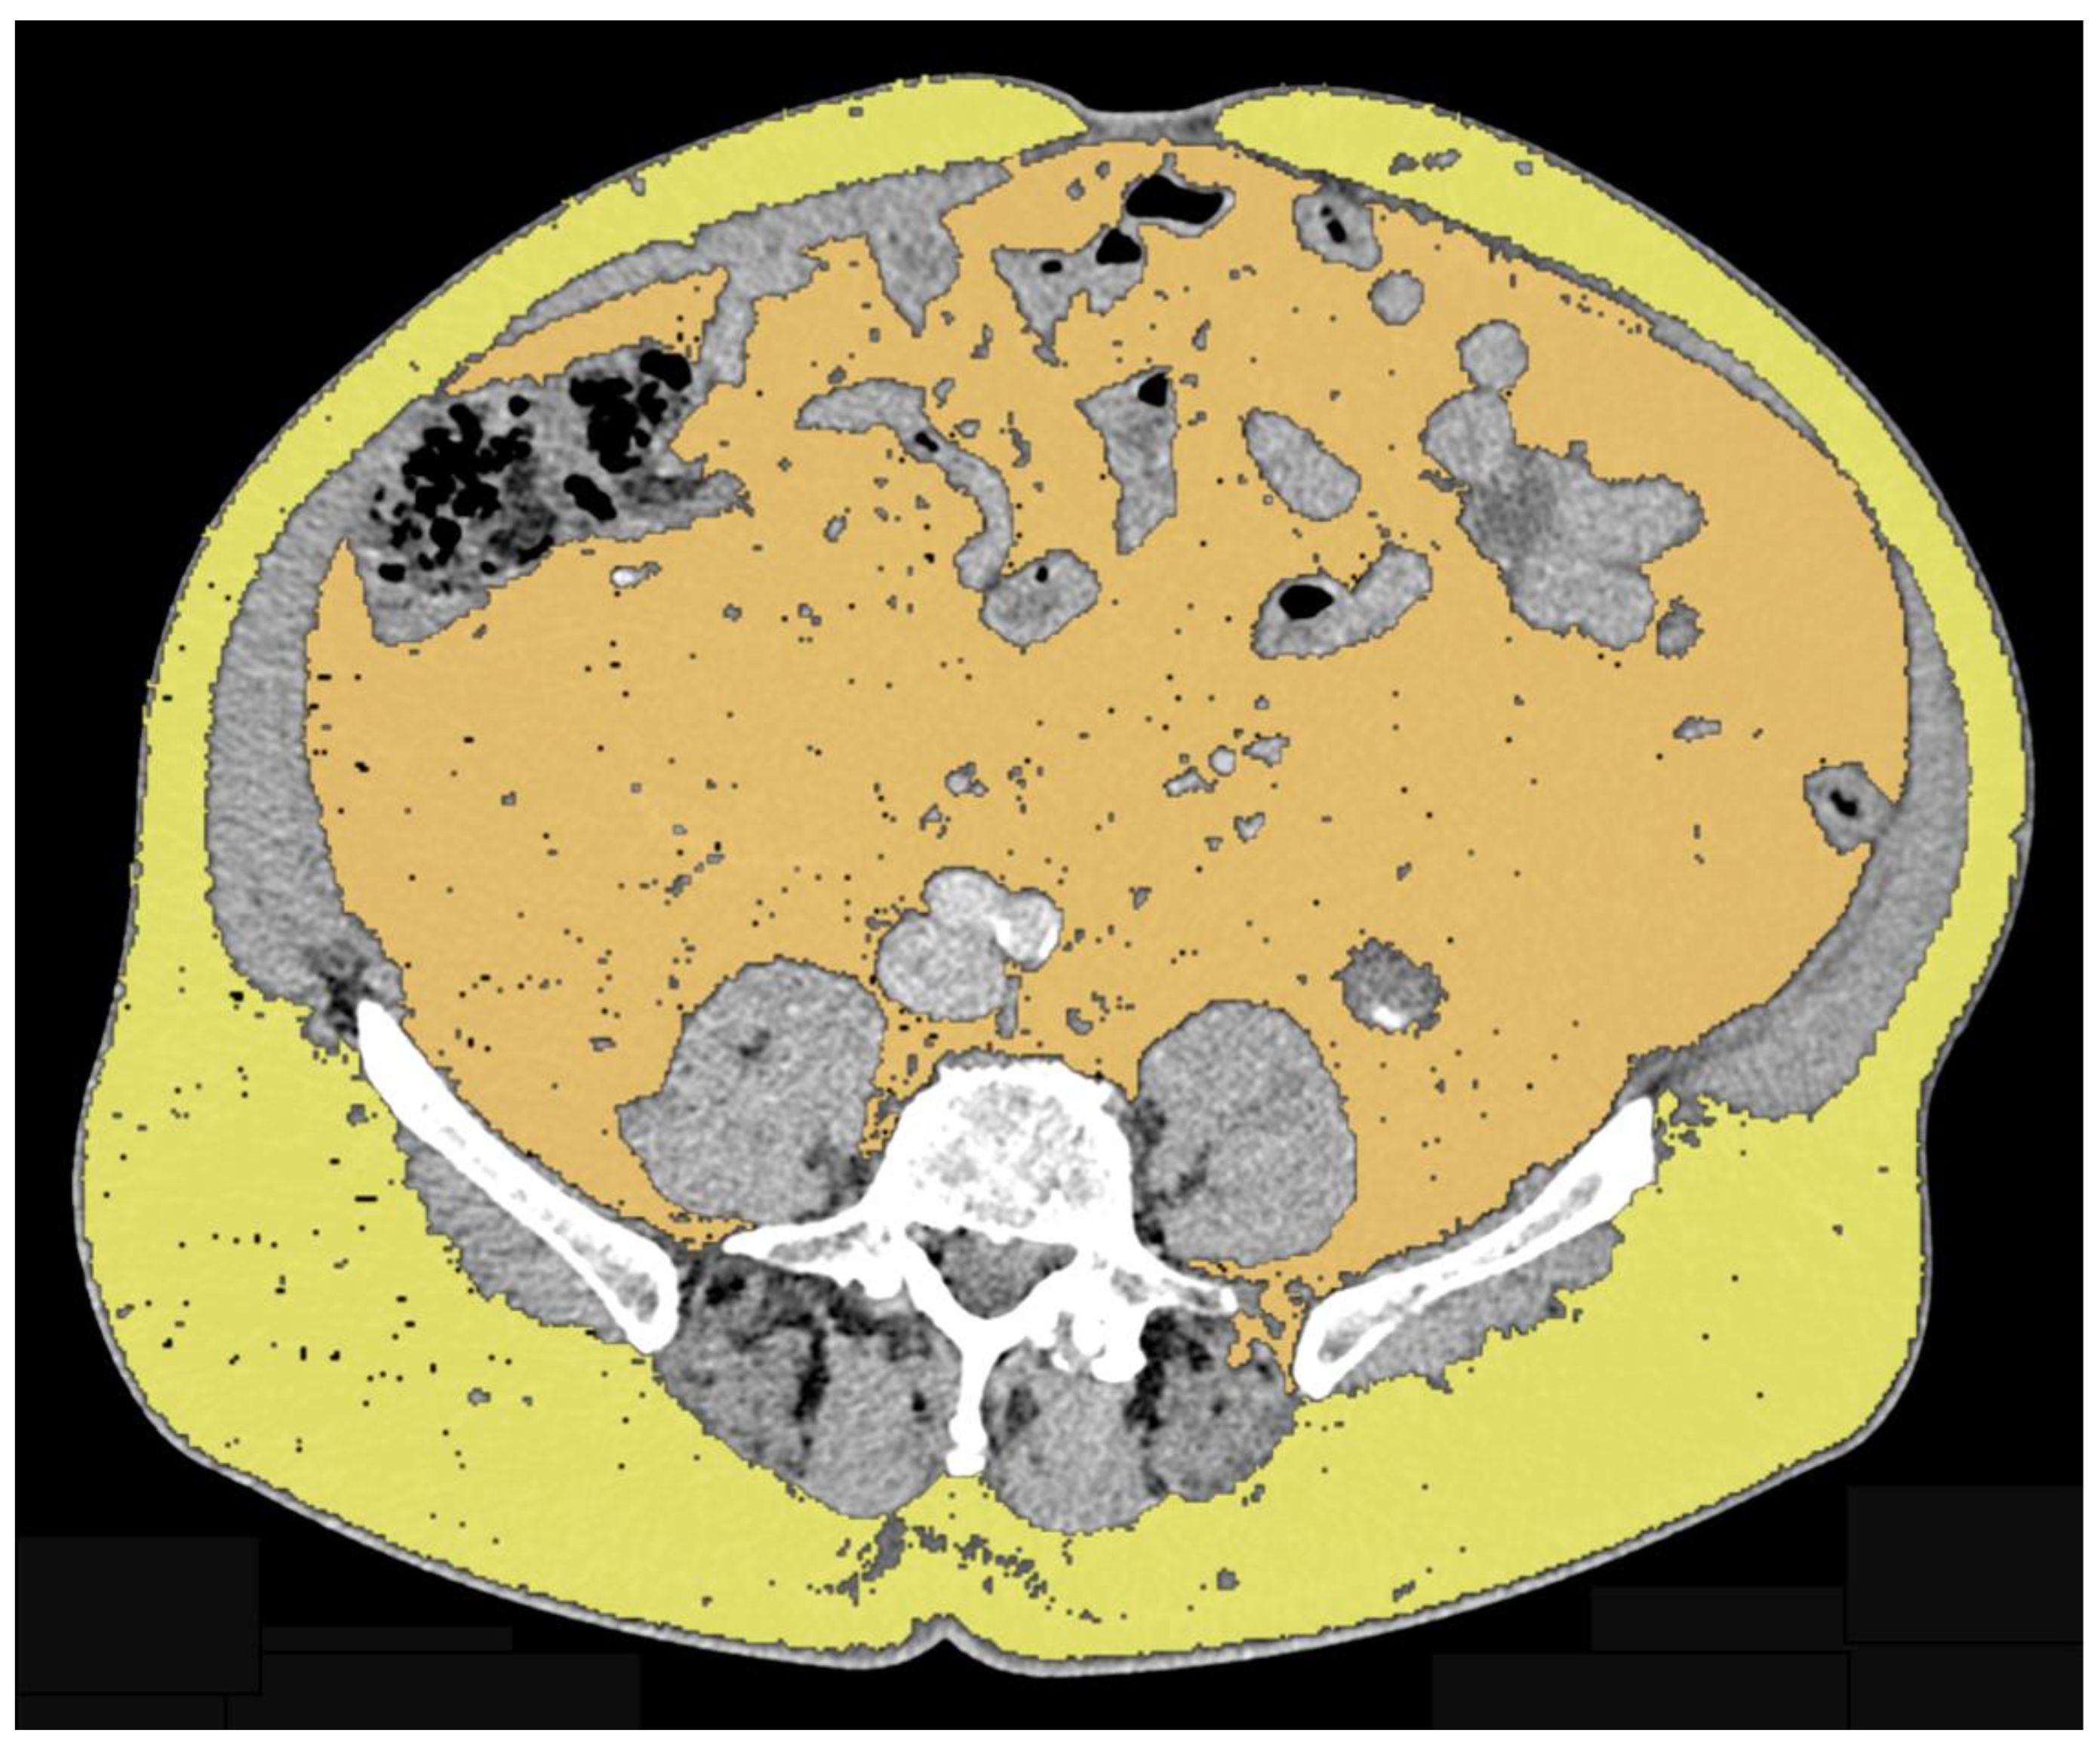

| Antoun et al. (2015) [18] | Abiraterone acetateEnzalutamide | VAT SAT | Area at L3 level on axial plane using CT-based approach | 46 | Decrease in SAT (p < 0.001) Increase in VAT (p = 0.01) |

| Sasaki et al. (2020) [21] | Luteinizing hormone-releasing hormone agonist or antagonist Androgen blockade | Periprostatic adipose tissue thickness SAT thickness VAT SAT | Periprostatic fat thickness was measured on T2-weighted axial images at the femoral head and greater trochanter of the femur levels SAT thickness was measured on T2-weighted axial images at the maximum diameter of the bladder level VAT and SAT areas area were measured on axial plane using CT-based approach at the level of the umbilical position | 85 | Periprostatic adipose tissue/SAT thickness ratio ≥ 1 and overall survival Periprostatic adipose tissue/SAT thickness ratio < 1 and overall survival Univariate hazard ratio and multivariate hazard ratio showed p = 0.043 and p = 0.002, respectively VAT/SAT thickness ratio ≥ 1 and <1: no significant difference |

| Sheikhbahaei et al. (2021) [19] | Docetaxel Abiraterone Prednisone | TAT VAT SAT | Area at L3 level on axial plane using CT-based approach | 22 | Increased SAT areas on first and second follow-up CT exams (p = 0.002 and p < 0.001, respectively) Increased TAT area on second follow-up compared to baseline (p < 0.001) No significant change in VAT areas |